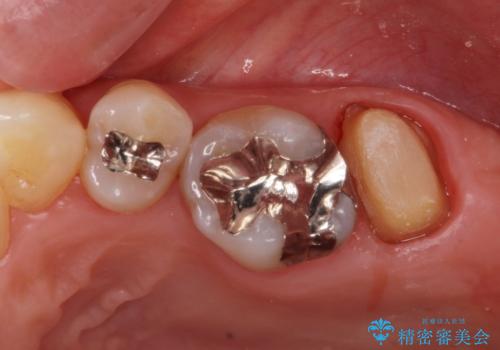

銀歯を白くしたいセラミック治療。

- 奥の銀歯を白くしたいとの事で来院。

痛みはないとの事でしたがレントゲンを撮影したところ根の先に病巣がある事がわかりました。

被せ物、古い材料を徹底的に除去し、ラバーダム防湿にて無菌的処置を行い、セラミックの被せ物で治療を行いました。